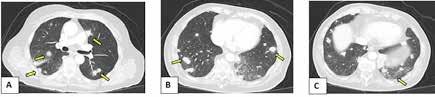

Figura 2. (Izq.) radiografía de tórax en proyección AP a las 36 horas de vida donde se objetiva neumotórax de nueva aparición (flechas azules) y una zona de hiperclaridad alrededor de la silueta cardíaca que sugiere importante neumomediastino (estrellas amarillas). (Der.) TC de tórax sin contraste intravenoso en ventana de pulmón que confirma la presencia de neumomediastino (estrella amarilla). Se objetivan focos de consolidación periféricos y bandas lineales de densidad aire paralelas y adyacentes a las vainas broncovasculares (flechas amarillas).